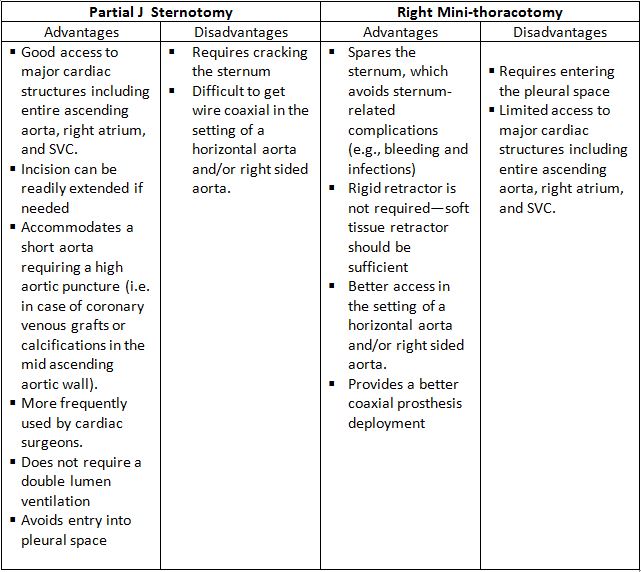

There are two minimally invasive surgical approaches: partial J-sternotomy and right minithoracotomy (Figure 4).

Table 1. Advantages and Disadvantages of the Partial J Sternotomy and Right Mini-thoracotomy

Fig. 4 Ministernotomy (right) and minithoracothomy (left).